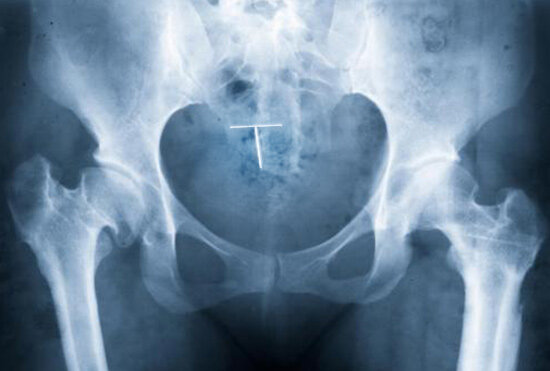

При проведении УЗ-исследования спираль четко визуализируется. Если в полости матки ее не обнаружили, значит, спирали там нет. Соответственно, выпасть контрацептив может только наружу и никуда более. Экспульсия, действительно, могла произойти во время контакта, при тяжелой физической нагрузке, во время очередных месячных, во время дефекации, в случае задержки стула.

Бывают редкие ситуации, когда при установке контрацептива происходит частичная или полная перфорация спиралью самой матки: неполноценная мышечная ткань в результате заболевания, атрофии, послеоперационных рубцов или аномалий развития органа. Но в этом случае, как правило, возникает клиника «острого живота». Подтверждается диагноз ультразвуковым исследованием, а лечение — хирургическое. На здоровой матке подобное — казуистика.

Что можно порекомендовать пациентке, «потерявшей» спираль? Повторить УЗИ органов малого таза у второго специалиста. В случае отсутствия патологии и отсутствия контрацептива в матке, расценивать ситуацию как экспульсию ВМК.